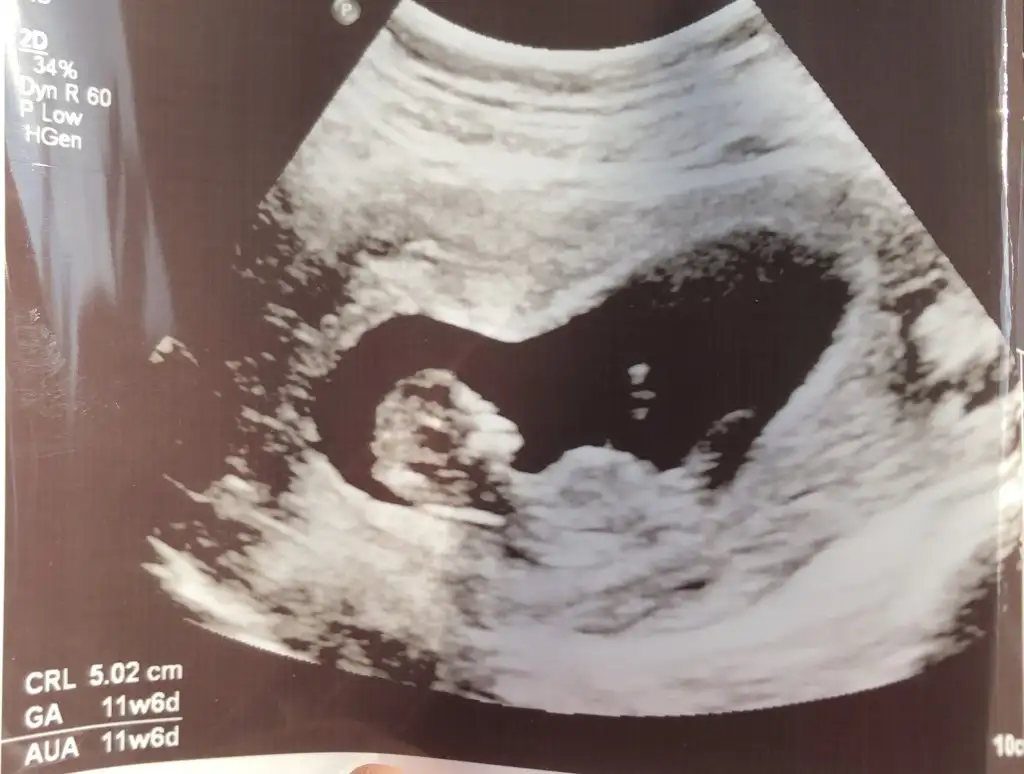

11 haftalık görüntüsü var mı cinsiyeti tahmin edecek olan☺️

Eklentiler

• 1C1E58D1-FC79-46C4-BA5E-4FDC4D5BE422.webp

1C1E58D1-FC79-46C4-BA5E-4FDC4D5BE422.webp

27,8 KB · Görüntüleme: 88

• 6D68836D-1FAE-42B4-9041-378E4BF167FA.webp

6D68836D-1FAE-42B4-9041-378E4BF167FA.webp

26,4 KB · Görüntüleme: 84